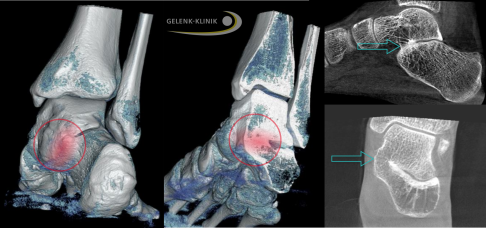

Magnetresonanztomographie (MRT) bei einem Patienten mit kompletter Koalition zwischen Sprungbein und Fersenbein (Kreis). Blick von hinten auf die Ferse: Rechts besteht eine nicht normale Verbindung der beiden Knochen. Man spricht von einer talokalkanearen Koalition. © Gelenk-Klinik

Magnetresonanztomographie (MRT) einer partiellen Koalition zwischen Sprungbein und Fersenbein (Pfeil) mit deutlichem Knochenödem als Zeichen einer akuten Entzündung. © Gelenk-Klinik